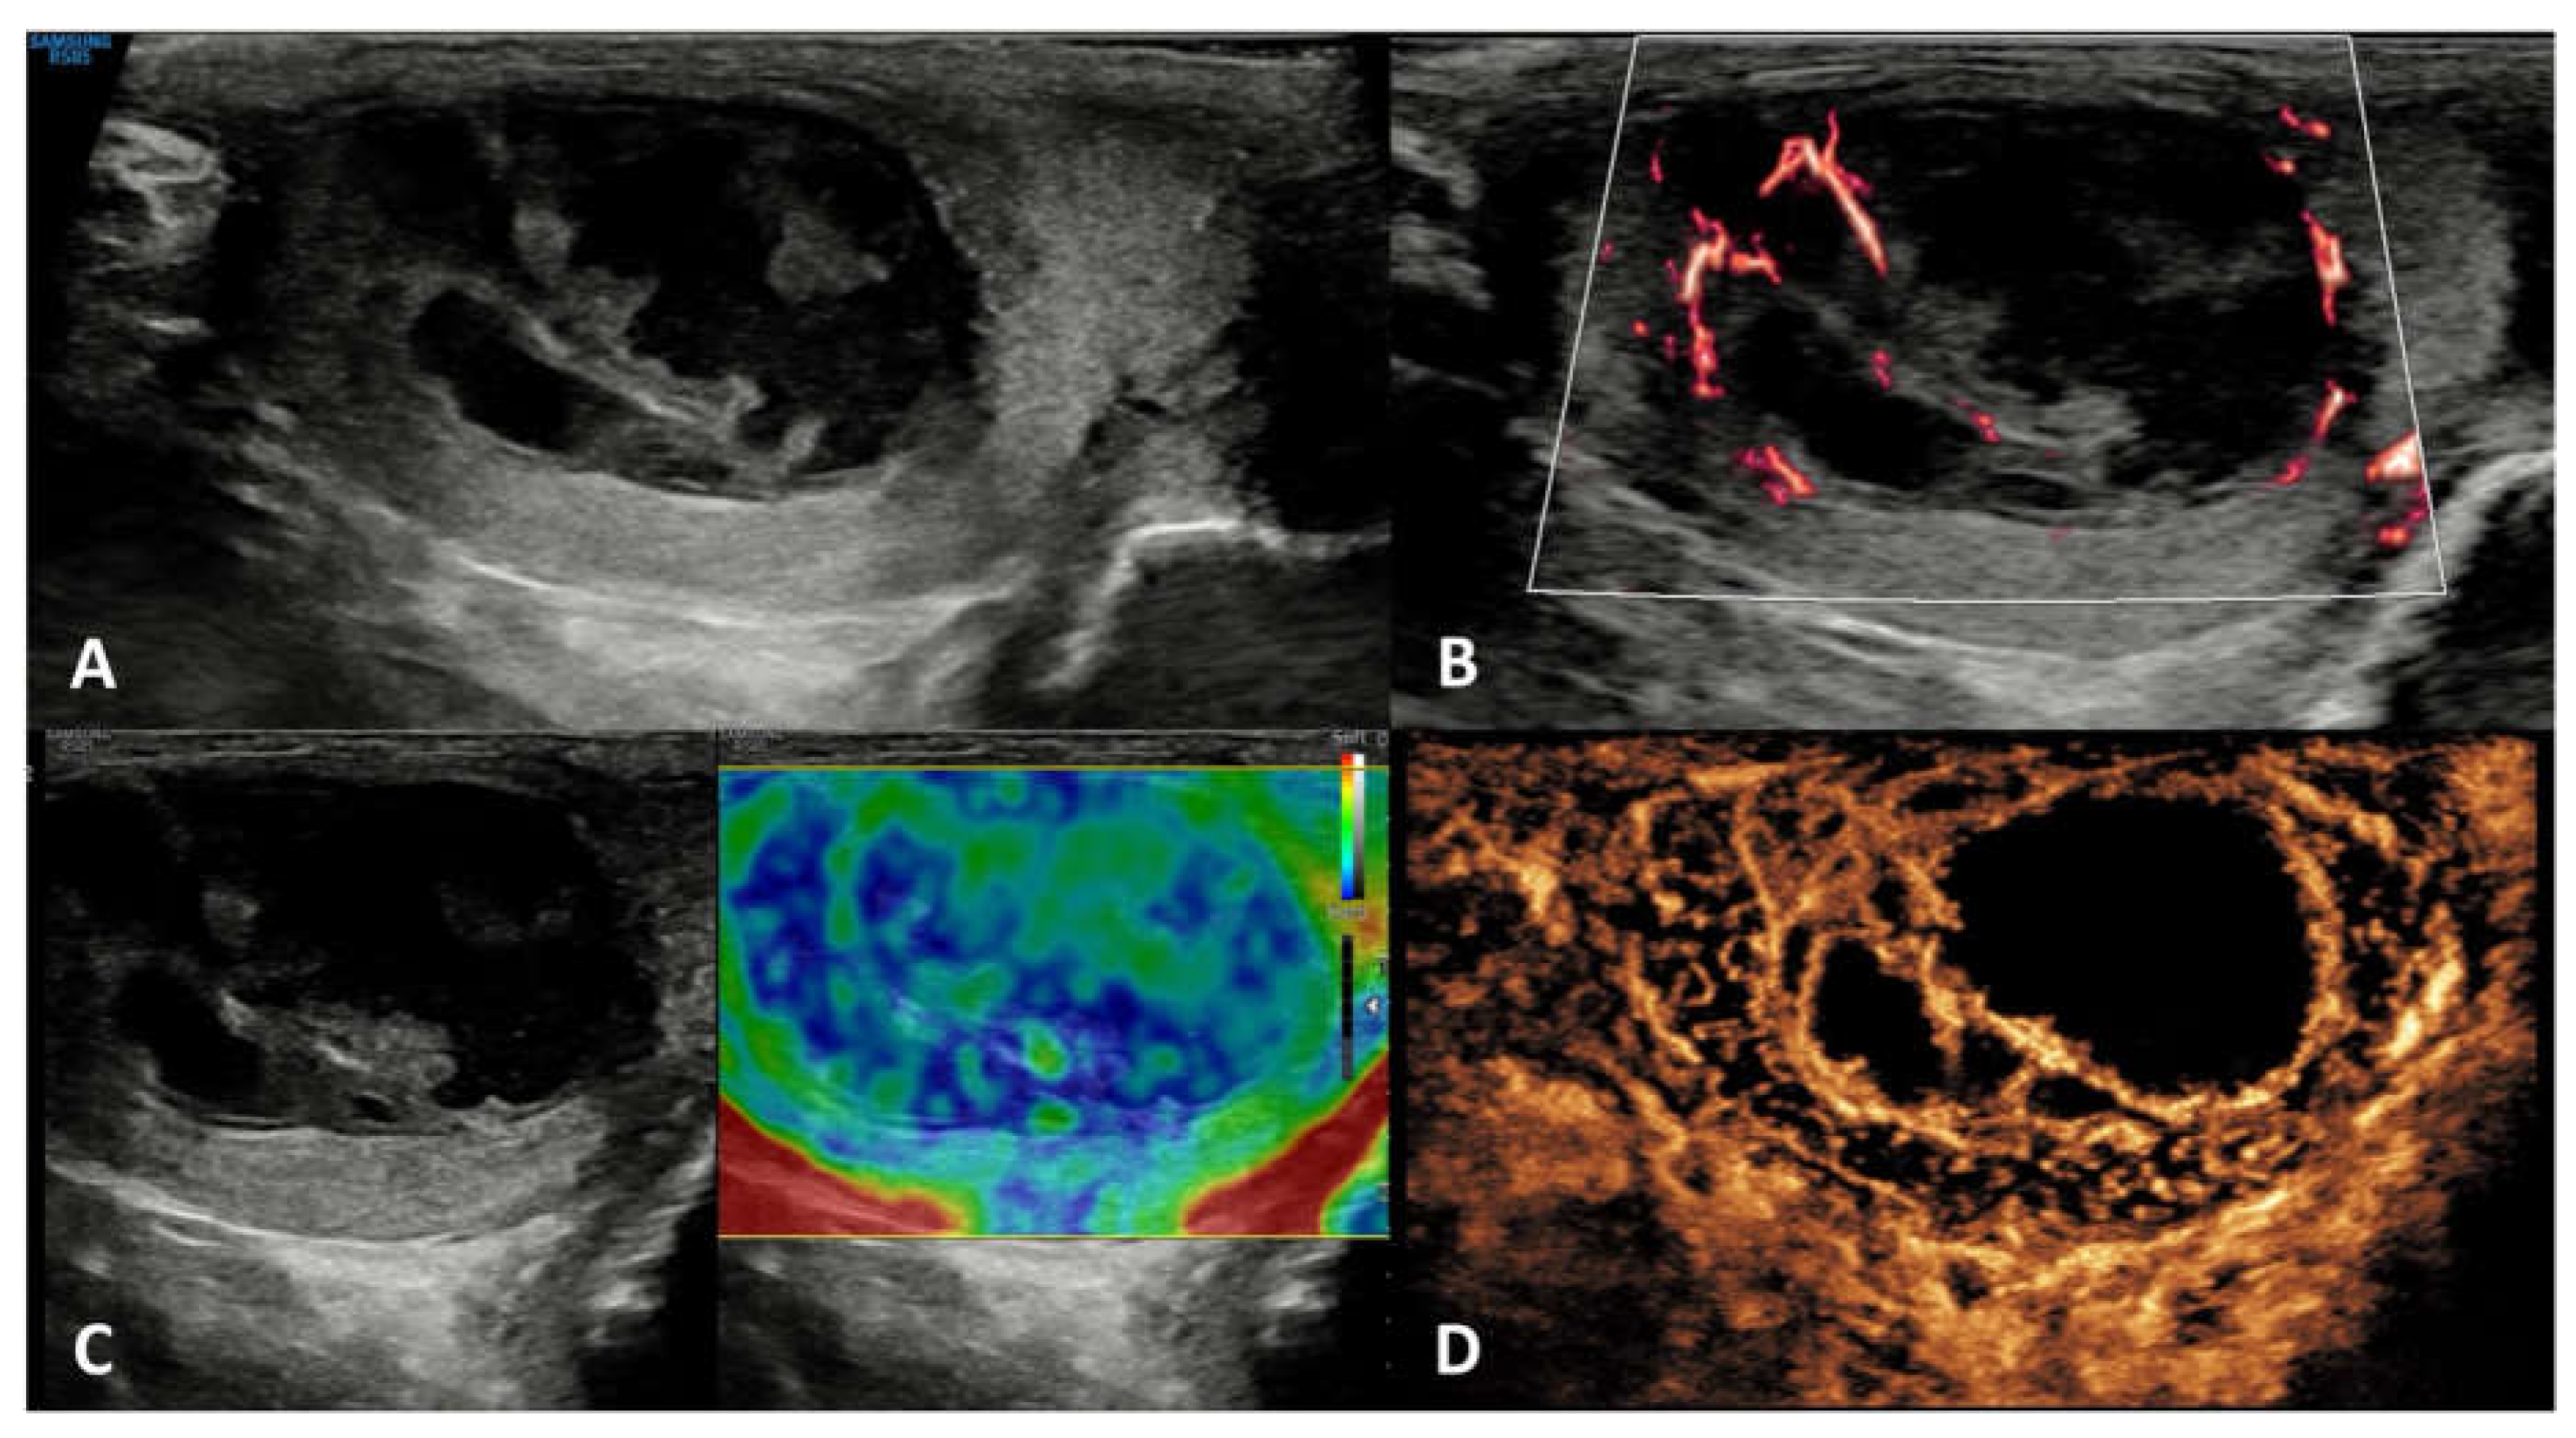

| Non-neoplastic intratesticular lesions | |||||

| Neoplastic intratesticular lesions | ||||||

|---|---|---|---|---|---|---|

| Clinical presentation | Serum tumor markers | GSUS | CDUS | CEUS | SE | |

| Leydig cell tumor | Generally asymptomatic; it can produce androgens | Negative | Hypoechoic, homogeneous well demarcated lesion (possible hyperechoic halo) |

Hypervascularized | Homogeneously hyperenhanced (rapid wash-in, delayed wash-out) |

Hard lesions with low/absent elastic strain |

| Sertoli cell tumor | Asymptomatic; they can be a part of multiple neoplasia syndromes, such as Carney Complex and Peutz-Jegers | Negative | Hypo- or hyper-echoic lesion, with possible calcifications | Hypervascularized | Homogeneously hyperenhanced |